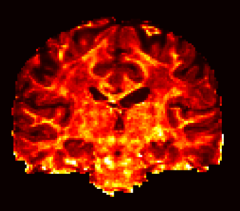

Figure 6 shows the intracellular and CSF volume fractions estimated using NODDI and NODDI-SH, respectively. The maps obtained with the two techniques are very similar. NODDI-SH intracellular volume fraction appears to be slightly more contrasted with respect to NODDI, in particular in single fiber areas such as the corpus callosum and the corticospinal tract. NODDI-SH CSF map presents more voxels with higher partial volume of CSF near the cortex, but in general, the agreement between the two maps is extremely high. For both models, CSF fraction maps present low, but non-zero, values in the white matter. Although the presence of free water between the axons is not likely, these values could be explained by an intrinsic error of the three compartment model used by both techniques.

| INTRACELLULAR | CSF | |

|

NODDI |

![]() |

|---|---|---|

NODDI-SH |